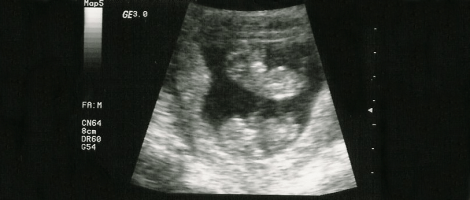

Nonostante questo, dato che non sono incinte fisicamente, ci sono una serie di sintomi che non sperimentano e che determinano la diagnosi della gravidanza isterica. Per esempio, non si sente il battito cardiaco del feto, non si vede nell'ecografia e non c'è parto, anche se alcuni studi assicurano che queste donne possono perfino sentire contrazioni.

La gravidanza isterica o fantasma si diagnostica in primo luogo verificando che non si tratti di una vera gestazione. Perciò, oltre all'esame fisico, il medico dovrà effettuare un test di gravidanza, un'ecografia e controllare le dimensioni dell'utero.